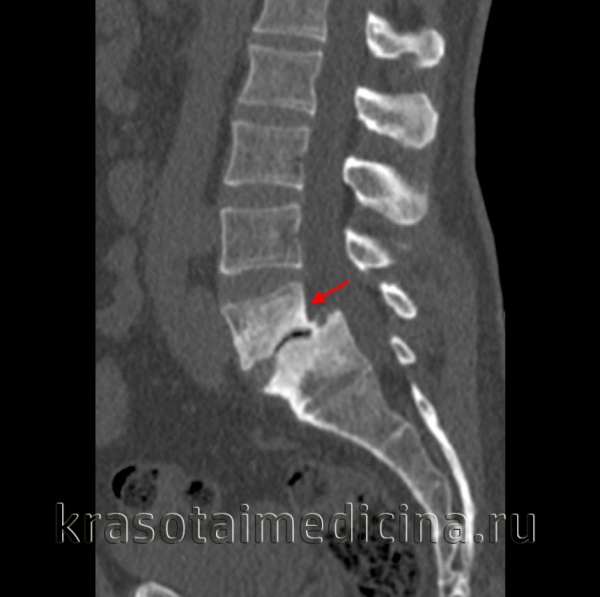

о Дефекты МЧ хорошо видны на косых реконструкциях

о Различной выраженности спондилолистез и фораминальный стеноз на сагиттальных реконструкциях:

- Снижение высоты межпозвонкового диска

- Дегенеративные изменения замыкательных пластинок

3. КТ при спондилолистезе:

• Костная КТ:

о Обращайте внимание на дефекты межсуставной части дуги, переломы, признаки стеноза позвоночника

(Справа) КТ, сагиттальный-срезе (костный режим): задний край тела L5 находится практически на одном уровне с передним краем S1. Хорошо виден дефект межсуставной части дуги, а также признаки выраженного стеноза межпозвонкового отверстия.